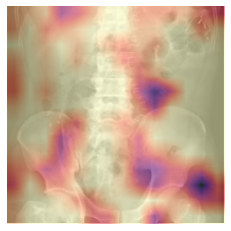

Grad-CAM

Gradient-weighted CAM (Grad-CAM) allows us to visualize the output from any convolutional block in a CNN.

By default, this cell is setup to show the Grad-CAM output from the final convolutional block in the CNN, for comparison to the CAM output.

Note: If you’re running this notebook in Colab, (1) choose which of the two test images you would like to examine and run this cell to see the Grad-CAM output overlayed on the input image, then (2) select a different block and re-run the cell to see how the output changes for different blocks in the network.

test_case = 'abd' #@param ['abd', 'chest']

cls = 0 if test_case == 'abd' else 1

label = test_case

y = get_image_files(path/'test'/label)

test_dl = learn.dls.test_dl(y, with_labels=True)

x, _ = first(test_dl)

mod = learn.model[0]

block = -2 #@param {type: "slider", min: -8, max: -1, step: 1}

hook_func = lambda m,i,o: o[0].detach().clone()

with Hook(mod[block], hook_func, is_forward=False) as hookg:

with Hook(mod[block], hook_func) as hook:

output = learn.model.eval()(x.cuda())

act = hook.stored

output[0, cls].backward()

grad = hookg.stored

w = grad[0].mean(dim=[1,2], keepdim=True)

cam_map = (w * act[0]).sum(0)

x_dec = TensorImage(dls.train.decode((x,))[0][0])

_, ax = plt.subplots()

x_dec.show(ctx=ax)

ax.imshow(cam_map.detach().cpu(), alpha=0.6, extent=(0,224,224,0),

interpolation='bilinear', cmap='magma');